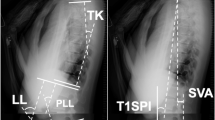

A 3-D patient-specific model was built (SterEOS software, Paris, France), which allowed the automatic computation of Cobb angle and multiple sagittal radiographic parameters, including cervical lordosis (CL), lumbar lordosis (LL), sagittal vertical axis (SVA), sacro-femoral distance (SFD), as well as the ratio between the C7 plumb line from the postero-superior corner of the sacrum and SFD (SVA/SFD) (Fig. 5A). Standard spinopelvic parameters were also computed: pelvic incidence (PI), pelvic tilt (PT), sacral slope (SS), and pelvic obliquity (Fig. 5B).

Illustration of measurements of spinal, pelvic and OD-HA parameters in sagittal radiography, including (A) CL cervical lordosis; TK thoracic kyphosis; LL lumbar lordosis; SVA sagittal vertical axis; SFD sacro-femoral distance; (B) PI pelvic incidence; SS sacral slope; PT pelvic tilt; and (C) OD-HA, odontoid-hip axis angle.